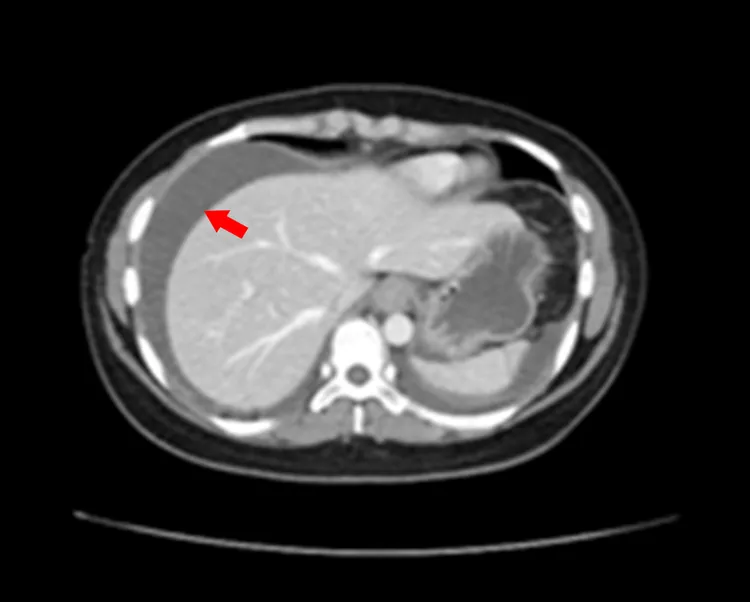

患者腹水情形嚴重(箭頭)。中港澄清醫院提供

李政祺醫師表示,這位女性患者在急診時抽血驗出她的白血球數高達23000(正常為400-10000),其中嗜酸性白血球比例29%(正常為5%),腹部電腦斷層發現小腸壁變厚且有明顯腹水情形,經收治住院治療。

李政祺說,該患者白血球很高,卻無發燒現象,應該不是典型的腸胃炎,因明顯腹水經抽出約800CC腹水並做化驗,發現嗜酸性白血球高達76%,經胃鏡取胃黏膜做切片檢驗,胃黏膜的嗜酸性球異常增加。人體白血球以嗜中性球和淋巴球占絕大多數,還有極少比例的嗜酸性球和嗜鹼性球,嗜酸性球過高又有腸胃發炎現象,排除其他原因後,確診為少見的「嗜酸性腸胃炎」。